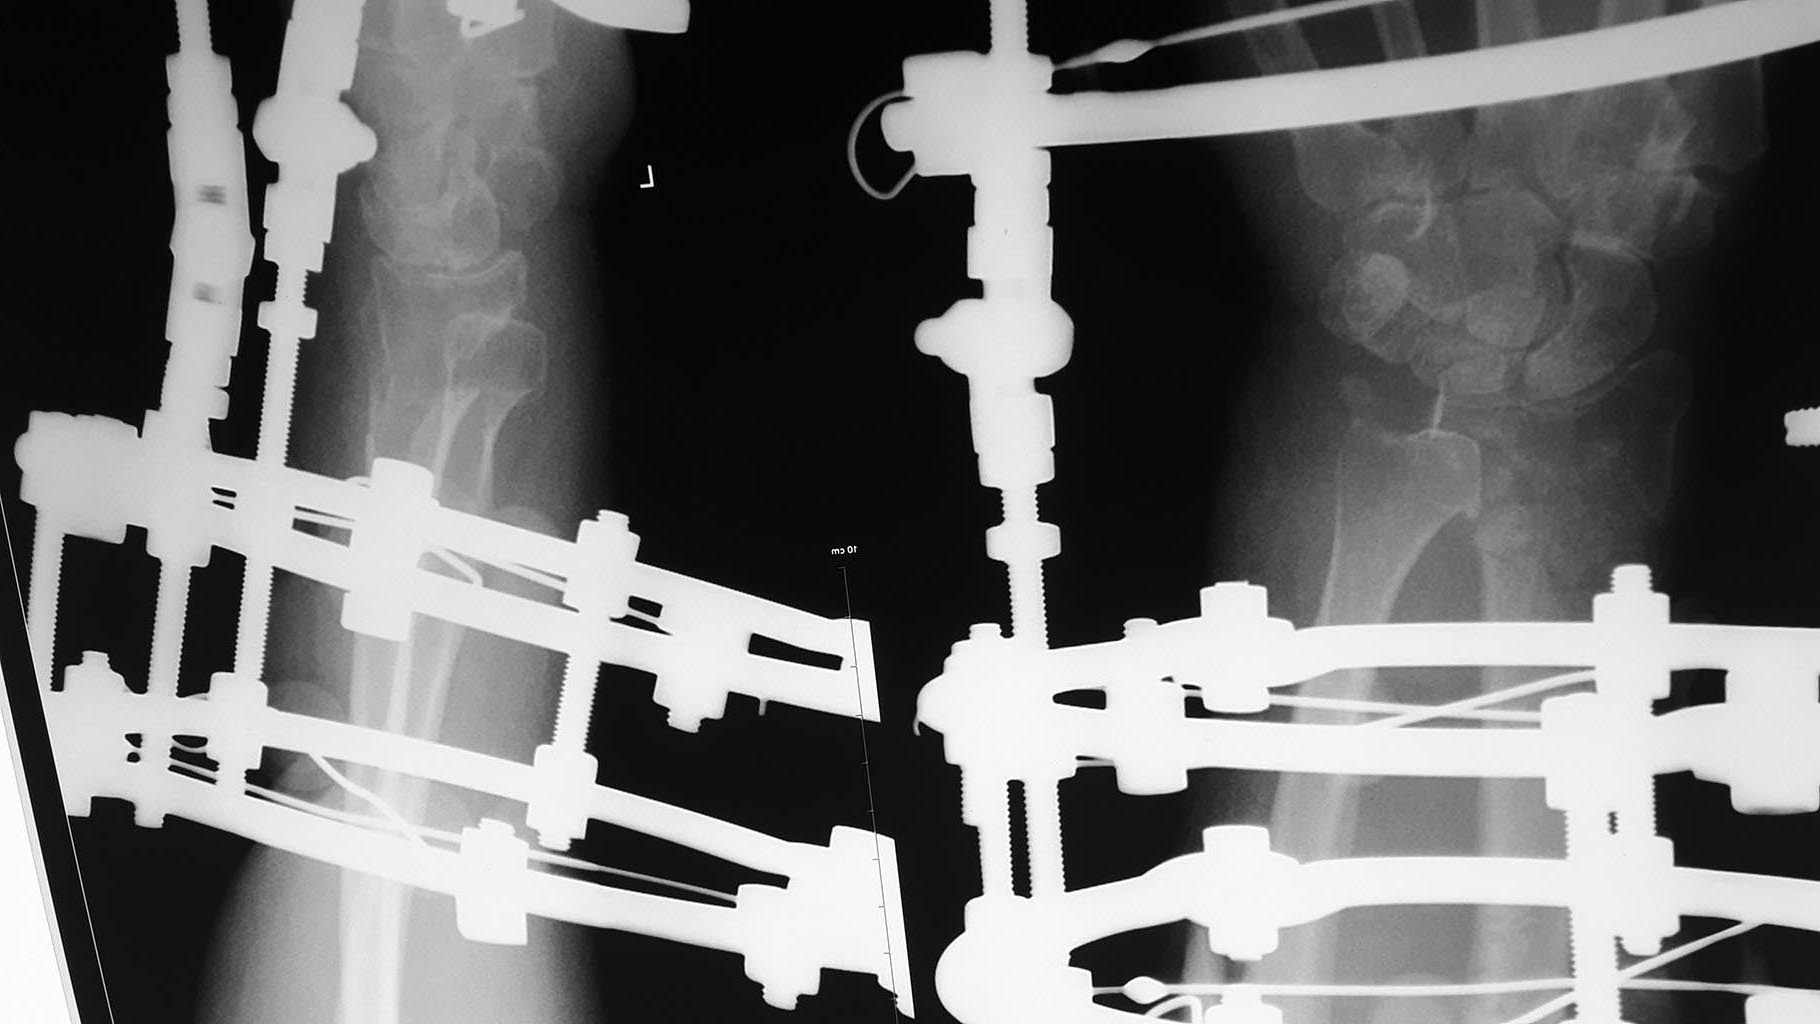

Пациентка 60 лет, 2 мес назад перелом дистального эпиметафиза лучевой

кости, шиловидного отростка, Наложен АВФ. По разным причинам продолжила

лечение у хирурга, который проводил дистракцию. Сожалею, первичные

снимки предоставить не могу. Рентген при поступлении и после "сброса"

дистракции. Сейчас думаем, что с этим делать,четкого плана пока нет,

какие у вас мысли по этому поводу?